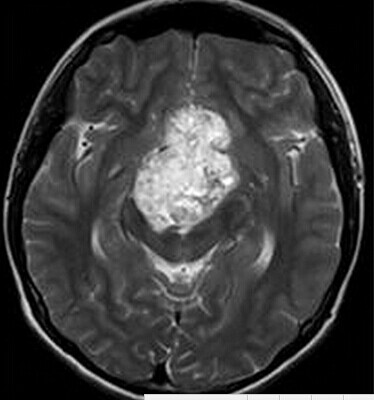

患者:男,15岁,双眼视力下降1年余,近来有嗜睡表现。

【正确答案】A 颅咽管瘤

(2)T1WI/T2WI上多为等信号,边界相对比较清楚;可见于第三脑室、鞍上、及鞍内,位于第三脑室者多体积较大,出现坏死、囊变,呈明显不均匀强化。

(1)颅咽管瘤的两个发病高峰年龄分别是4-15岁和35-45岁,其中实性颅咽管瘤多见于成年人,本例为青少年患者,发病年龄无特异性;

(2)对诊断有提示意义的征象是明显强化,内散在微囊状不强化区。